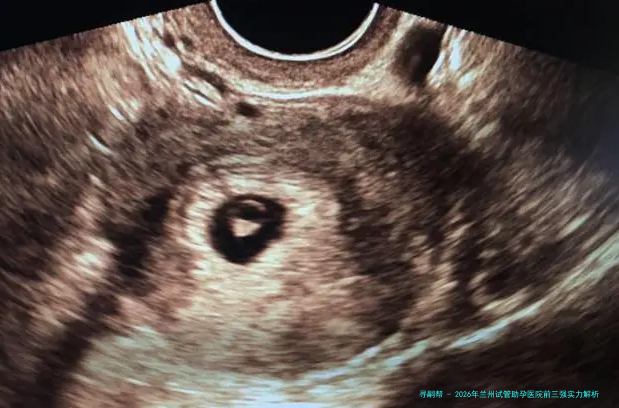

至于众多在生育路上碰见困顿的家庭来说,选定一家技术过硬、声誉优良的试管婴儿医院是迈向成功的步。在兰州,经过多年的发展,几家大型公立三甲医院在辅助生殖领域竖立了坚实的口碑。今天,我们就来详细认知一下兰州地区备受信赖的几家试管助孕医院,并为众人提供一份详尽的费用对照。